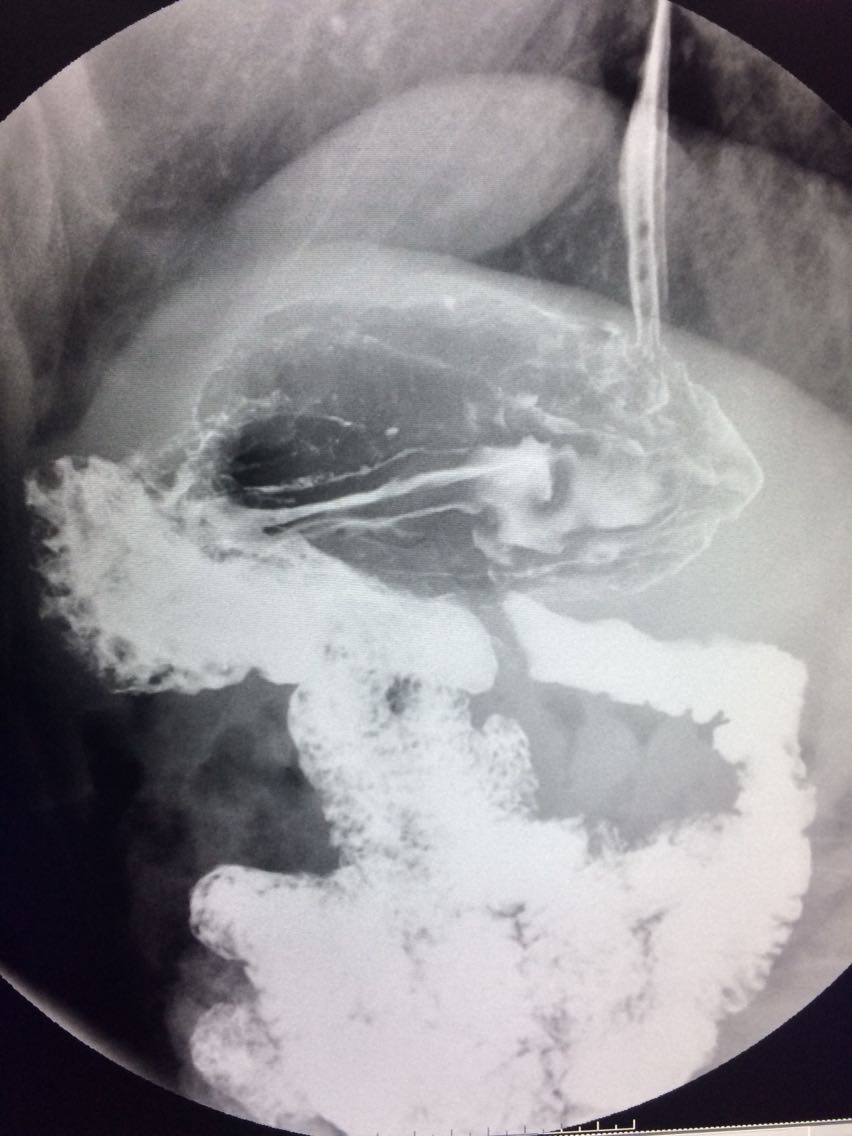

一例溃疡型胃癌。

男,45岁 反复胃疼5年余。 5年来,反复出现胃疼,进食后半小时加重,经常感觉饥饿,当地按胃溃疡,给予阿莫西林,奥美拉唑治疗,具体不详,效果欠佳,遂入院,入院来,饮食睡眠,二便可。 既往体健。 入院上消化道造影如图。

如图

讨论,诊断及鉴别诊断? 胃溃疡的影像表现? 溃疡良恶性的鉴别? 入院后行胃大部切除术。 诊断,胃腺癌。